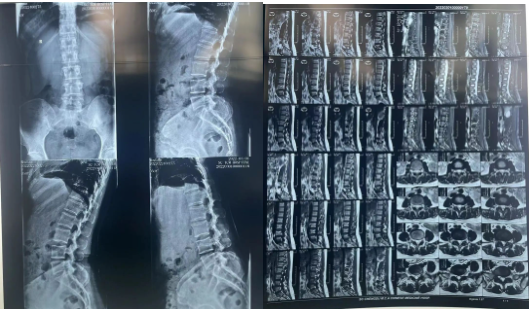

患者术前影像资料

余洋教授为患者行椎间孔镜下髓核摘除联合纤维环修复手术